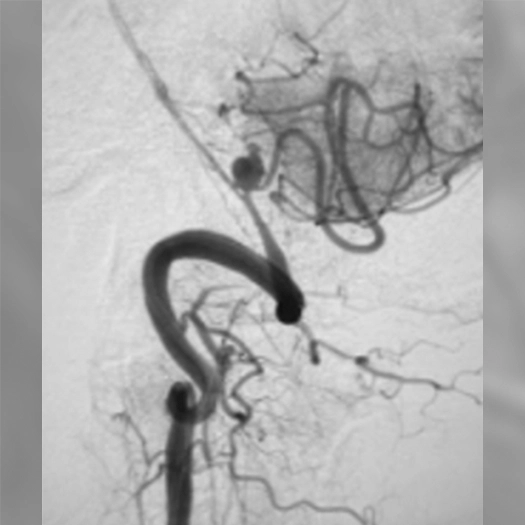

Proximal vessel sacrifice of LICA/LECA using POD400, PAC400, and PC400. A total of 877 cm of coil delivered by ACCESS25

Vessel Sacrifice

• POD400 + PAC400 for vessel sacrifice

• .020″ platform offered high volume and flexibility in case

• POD400 created a backstop, filled with PAC400

• BMX81 designed for stable vascular access